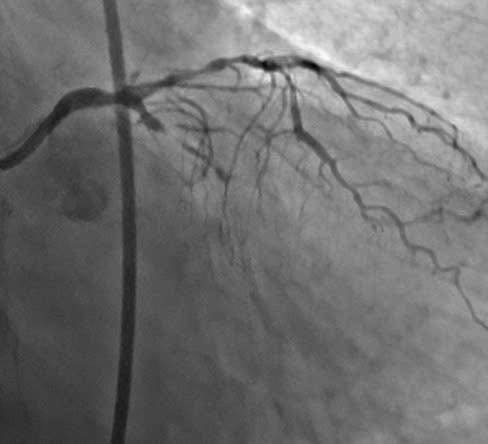

Tổn thương trước chụp động mạch vành - Ảnh BVCC

Kết quả chụp động mạch vành cho thấy động mạch liên thất trước (nhánh mạch máu quan trọng nhất của tim) bị hẹp khít tới 90%. Động mạch vành mũ đã bị tắc hoàn toàn mạn tính (CTO).

Điều này đồng nghĩa với việc hai trong ba nhánh chính nuôi tim đều bị tổn thương nghiêm trọng, đẩy trái tim vào tình trạng thiếu máu nuôi dưỡng có nguy cơ cao dẫn đến suy tim nặng, thậm chí tử vong bất cứ lúc nào.